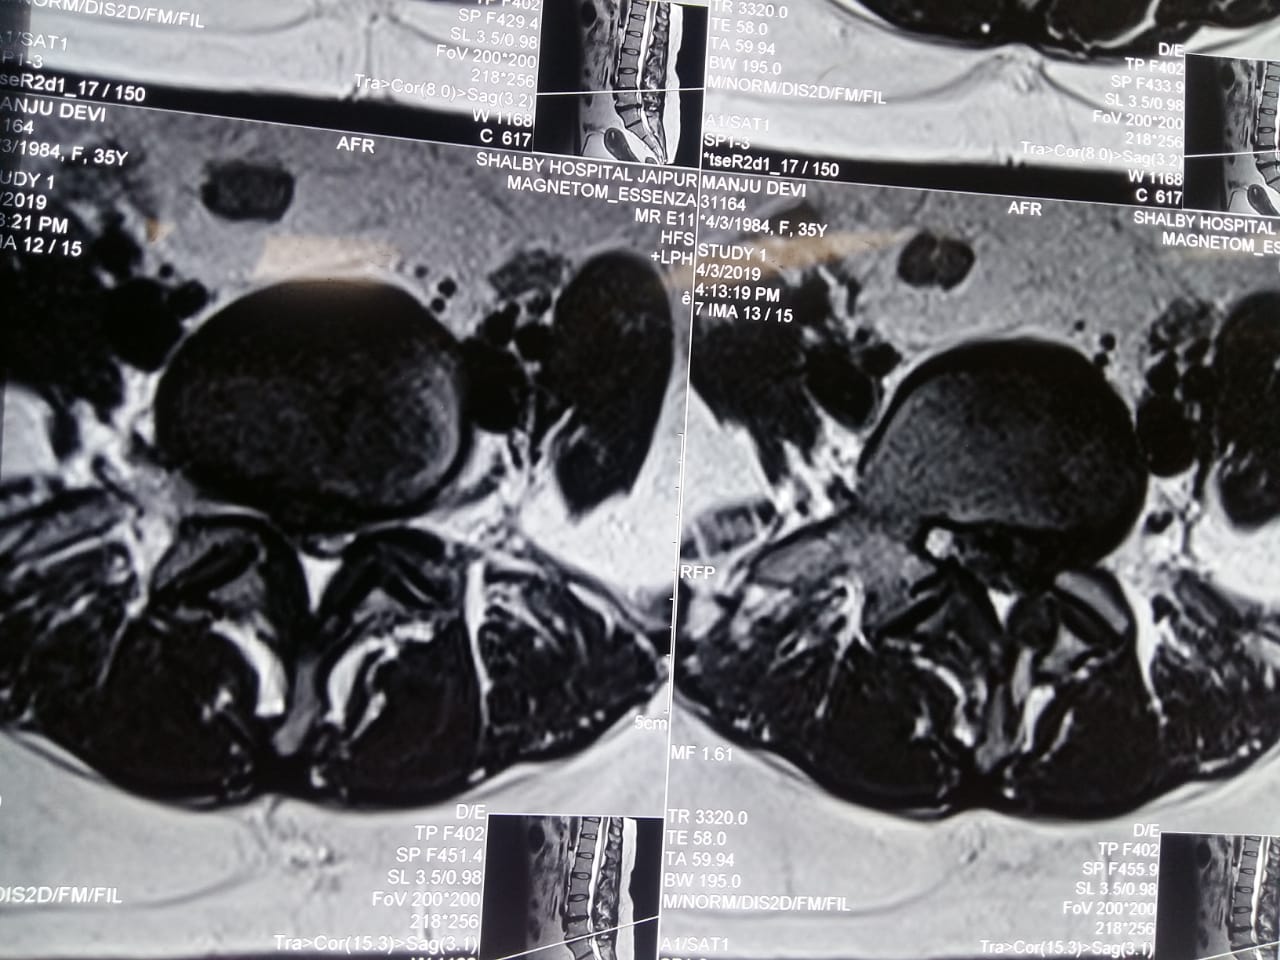

Big L5 S1 disc causing severe pain in left leg

MRI Showing slip disc